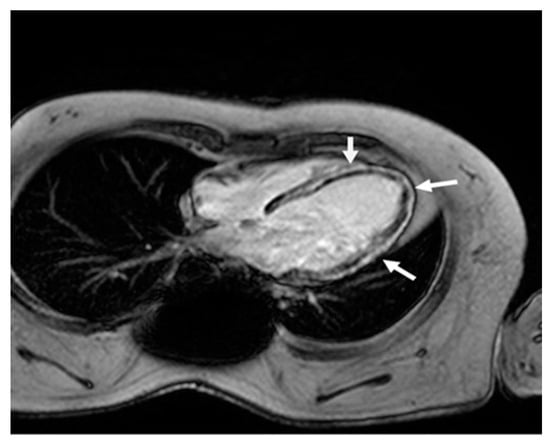

Figure 2.

Cardiac magnetic resonance four-chamber view. Late gadolinium enhancement in the left ventricle wall (arrows) in a typical non-ischemic (mid-wall) distribution, due to extensive myocardial fibrosis.